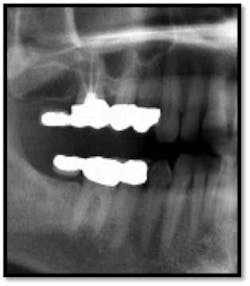

UR/LR Pre TxThe tissues around the posterior crowns are almost bluish in color(above left)UL/LL Pre Tx:

TX FM Perioscopy with local anesthetic FM LANAP Surgical Procedure •bone sounding was performed on all teeth included in this procedure •occlusal adjustment performed resulting in reduction in centric prematurities •Orthodontic referral for anterior spacing •3 month periodontal maintenance14 months post TreatmentPocket reductions of up to 4mm